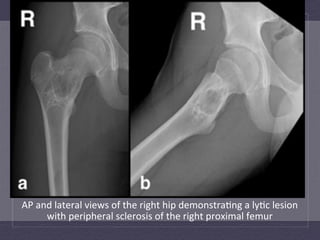

AP  and  lateral  views  of  the  right  hip  demonstra:ng  a  ly:c  lesion   with  peripheral  sclerosis  of  the  right  proximal  femur